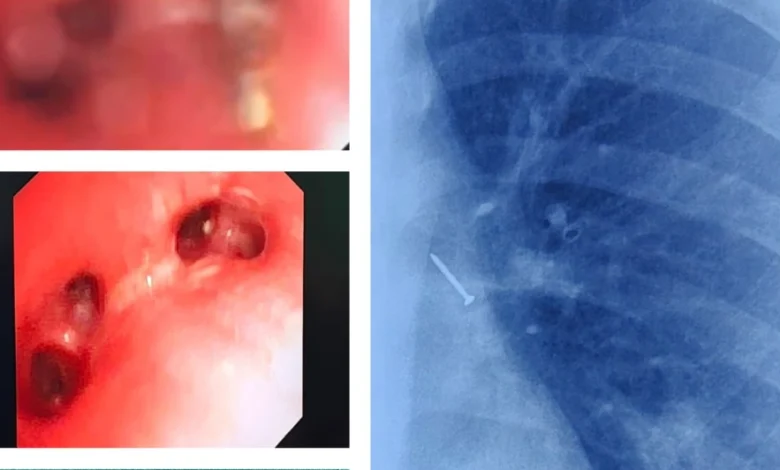

वीडियो ब्रोंकोस्कोपी ने बचाई जान-डॉक्टरों ने तुरंत वीडियो ब्रोंकोस्कोपी का सहारा लिया। यह एक ऐसी तकनीक है जिसमें एक छोटा कैमरा श्वास नली में डाला जाता है, जिससे डॉक्टर अंदर की स्थिति को साफ़ देख पाते हैं। इस प्रक्रिया के दौरान, बच्चे को सुरक्षित रखने के लिए विशेष सावधानियाँ बरती गईं। डॉक्टरों ने वीडियो ब्रोंकोस्कोपी की मदद से पिन का पता लगाया और उसे सावधानीपूर्वक बाहर निकाल लिया। इस दौरान मामूली रक्तस्राव हुआ, जिसे तुरंत नियंत्रित कर लिया गया।

एक संयुक्त प्रयास-इस जटिल ऑपरेशन में कई डॉक्टरों और विशेषज्ञों की टीम ने मिलकर काम किया। एनेस्थीसिया टीम ने बच्चे की सांसों का ध्यान रखा, और रेडियोलॉजी विभाग ने फेफड़ों की स्थिति का सही आकलन करने में मदद की। यह एक संयुक्त प्रयास था जिसने बच्चे की जान बचाई।